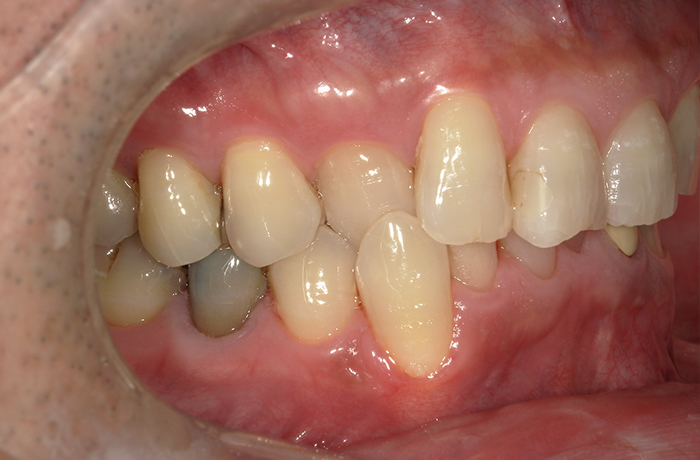

治療前

口腔内写真とレントゲン写真

左上6・7番欠損部は骨吸収が進行し、上顎洞底までの残存骨高径は5mm未満でした。

咬合支持が失われ、対合歯の挺出傾向がありました。